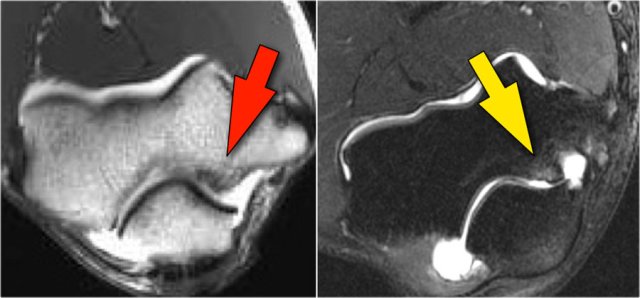

Arthrosis in valgus overload syndrome

Due to the valgus overload there are shear forces on the posteromedial part of the humeroulnar joint.

Notice the subchondral sclerosis seen on the T1W-image (red arrow).

On the T2W-image there is subchondral bone marrow edema and cartilage loss (yellow arrow).

These are images of a 20 year old baseball pitcher.

Scroll through the images.

On the coronal images there is a beautiful anterior bundle of the UCL, but notice that there is osteophyte formation on the medial part of the joint (red arrow).

As we go further posteriorly there is a small area of low signal intensity (yellow arrow), which is an avulsion of part of the UCL.

This is better appreciated on the radiograph.

Continue with the axial scan.

As we look on the axial scan, we can appreciate the huge osteophyte formation.

Notice that the ulnar nerve (blue arrow) is next to these osteophytes and these patients may present with ulnar neuropathy.